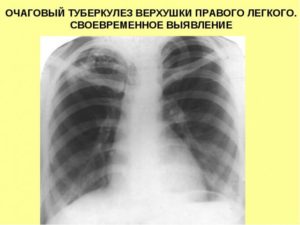

Очаговый туберкулез легких: заразен или нет, лечение в фазе инфильтрации, двухсторонний рентген, симптомы распада верхней доли правого легкого

Очаговый туберкулез легких — это вид вторичного заболевания, которое протекает с образованием в органах дыхания воспалительных очагов. В большинстве случаев болезнь практически не имеет выраженных симптомов, поэтому нередко ее выявляют при флюорографическом обследовании.

Чаще всего диагностируется очаговый туберкулез верхней доли правого легкого.

Рентгенологические признаки

Пациенту проводят рентген легких в 2 проекциях. При свежем заболевании на снимке очаги представлены в виде теневых образований небольшого и крупного размера, имеющих округлую форму.

Нередко они локализуются в верхних отделах легких. Для хронической формы патологии характерны плотные фокусы с очагами фиброзных тяжей.